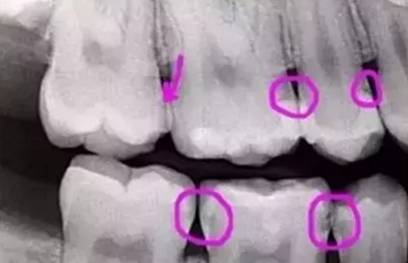

下图圈出来的地方就是龋齿,

这些都在牙缝之间,

直接用眼睛基本看不到